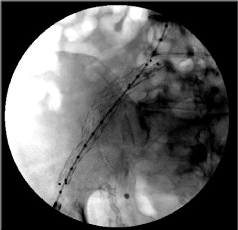

Our patient is a 49-year-old male with a long history of insulin-dependent diabetes mellitus (IDDM) complicated by diabetic nephropathy and end-stage renal disease (ESRD) on hemodialysis. After a standard preoperative pre-transplant process, he was found to have a matched cadaveric donor and underwent a combined kidney and pancreas transplant. The pancreatic graft was enterically drained and the kidney was placed in the left lower abdomen in the traditional manner. The first two weeks of postoperative course were complicated by pancreatic graft thrombosis and ureteral leak, requiring pancreatectomy, right common iliac artery repair with a bovine patch, and repair of the ureteral leak with nephrostomy tube placement. After being discharged from the hospital, he had a slow recovery, requiring close monitoring and frequent follow up appointments. Fourteen months after the initial surgery, he presented to the emergency room complaining of abdominal pain after a fall. Due to concern of organ damage from blunt trauma to the abdomen, a computerized tomography scan (CT) of the abdomen and pelvis with intravenous contrast was performed which showed a pseudoaneurysm arising off the right common iliac artery with free pelvic fluid concerning for an associated leak (Figure 1). There was also demarcation of the sigmoid colon with contrast despite the lack of administration of oral contrast. No definitive fistulous tract was seen; however, an arterio-enteric fistula was highly suspected based on the history of the arterial wall patch repair. The patient remained hemodynamically stable without evidence of gastrointestinal bleeding. Vascular surgery was consulted, and an emergency retrograde pelvic angiogram and aortogram was performed through an ipsilateral catheterization of right external iliac artery. Identification of a pseudoaneurysm adjacent to the repair of the right common iliac artery raised concern of a pressure-erosion mechanism for the creation of the arterio-colonic fistula, which at the time was not involving all the layers of the bowel wall, but instead dissecting through the sigmoid colon wall. Because of these particular findings of the fistula, with partial colonic wall involvement, the decision was made to place an intravascular stent graft to cover the area of connection between the pseudoaneurysm and the sigmoid colon. An exclusion stent graft was deployed in the right common iliac/external iliac artery pseudoaneurysm, utilizing the same system used for the endovascular treatment of infrarenal abdominal aortic or aortoiliac aneurysms (Endurant II® contralateral limb stent graft; 16 × 10 × 156 mm - Medtronic) as shown in Figure 2. This procedure was performed as a temporary control measure, to decrease the possibilities of a massive lower gastrointestinal bleeding. Although a true communication with the colonic mucosa and bowel lumen was not proven, the likelihood of graft infection was assumed to be high, therefore, once having a better control of the fistula, the plan was to proceed with definitive surgical repair in the near future.

Figure 1: Computer tomography scan of abdomen and pelvis with intravenous contrast, coronal view. Demonstrating a pseudoaneurysm arising off right common iliac artery (short red arrow) with free pelvic fluid concerning for an associated leak from the pseudoaneurysm. Demarcation of the sigmoid colon with contrast (long yellow arrow) in close proximity to the pseudoaneurysm. View Figure 1